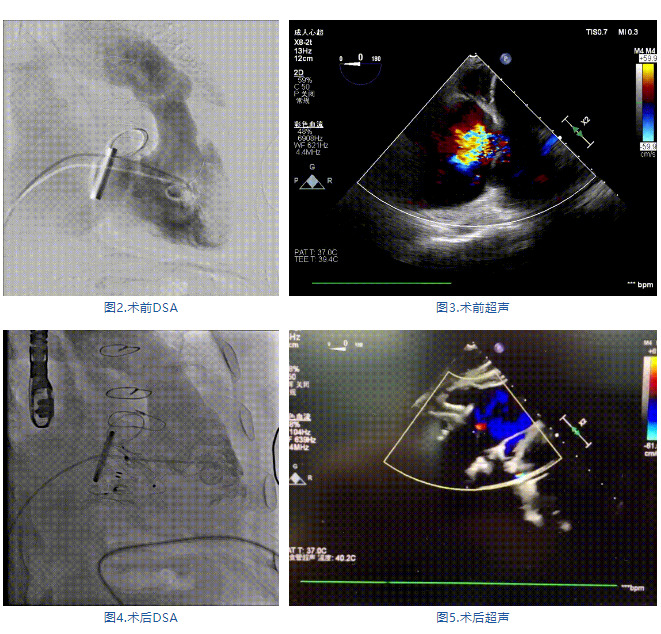

手術(shù)在全麻狀態(tài)下進行,郭惠明教授團隊采用經(jīng)右側(cè)頸靜脈入路的方式送入輸送器進入體內(nèi),并在TEE和DSA的指引下進行。在輸送器進入右室后釋放室間隔錨定裝置,旋轉(zhuǎn)輸送器,使得錨定裝置對準室間隔面;而后釋放前瓣夾持件,確定夾持件位于右室側(cè)釋放LuX-Valve Plus人工瓣膜盤片,再使用DSA和超聲確認盤片是否位于右房側(cè),同時調(diào)整瓣膜的同軸性。緊接著在DSA和超聲的監(jiān)視下調(diào)整室間隔錨定件貼合室間隔,釋放室間隔錨定裝置。再次確認瓣膜的穩(wěn)定性和同軸性后,將輸送器撤出體內(nèi),最終完成LuX-Valve Plus人工瓣膜植入(圖2-5),手術(shù)獲得圓滿成功?;颊咴谑中g(shù)室即刻拔除氣管插管,術(shù)后超聲提示LuX-Valve Plus人工三尖瓣瓣膜同軸性良好,瓣架固定牢靠,無反流和瓣周漏。